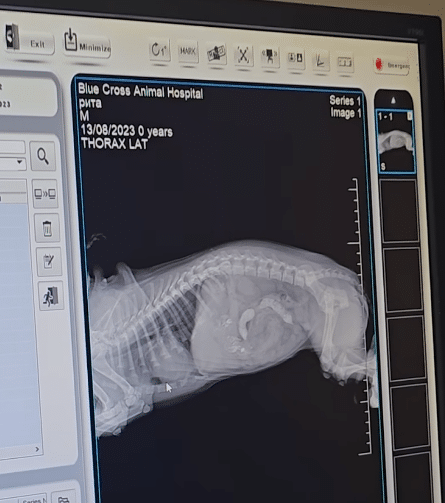

An X-ray was taken.

No fractures.

Not a single broken bone.

It felt like a miracle.

Whatever had caused her collapse, it had not shattered her body.

She was fragile — but intact.